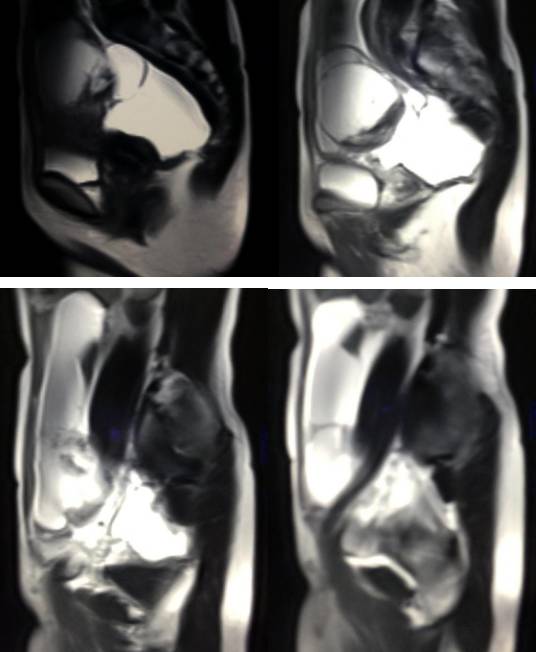

MR检查:

病理结果:黄体血肿

黄体血肿为正常排卵过程中,卵泡层破裂,引起出血,较多的血液潴留在卵泡或黄体腔内形成血肿。

正常黄体直径为15mm左右,以后转变为白体,并在下一个周期的卵泡期自然消退。若黄体内出血量较多,则形成黄体血肿,或称黄体内出血,出血性黄体。黄体血肿多为单侧,一般直径为40mm,偶可达100mm,黄体血肿被吸收后可导致黄体囊肿,较大的血肿破裂时可出现腹腔内出血,剧烈腹痛、少量阴道流血和腹膜刺激征,不易与宫外孕区别。

黄体血肿早期:囊内出血较多时,表现为卵巢内近圆形囊肿,囊壁厚,内壁粗糙。

黄体血肿中期:黄体血肿内血液凝固,部分吸收,囊壁变薄而,内壁光滑。

黄体血肿晚期:血液吸收后囊肿变小,转变为白体,内部回声呈实性稍高回

声,与周围卵巢组织分界不清,面靠彩超显示其周围环状血流判断,当血液完全吸收后形成黄体囊肿,囊壁变得光滑,与卵巢其他囊肿难以区分。

根据时间不同MR信号也有所不同,TIWI脂肪抑制序列可以鉴别脂肪和出血。